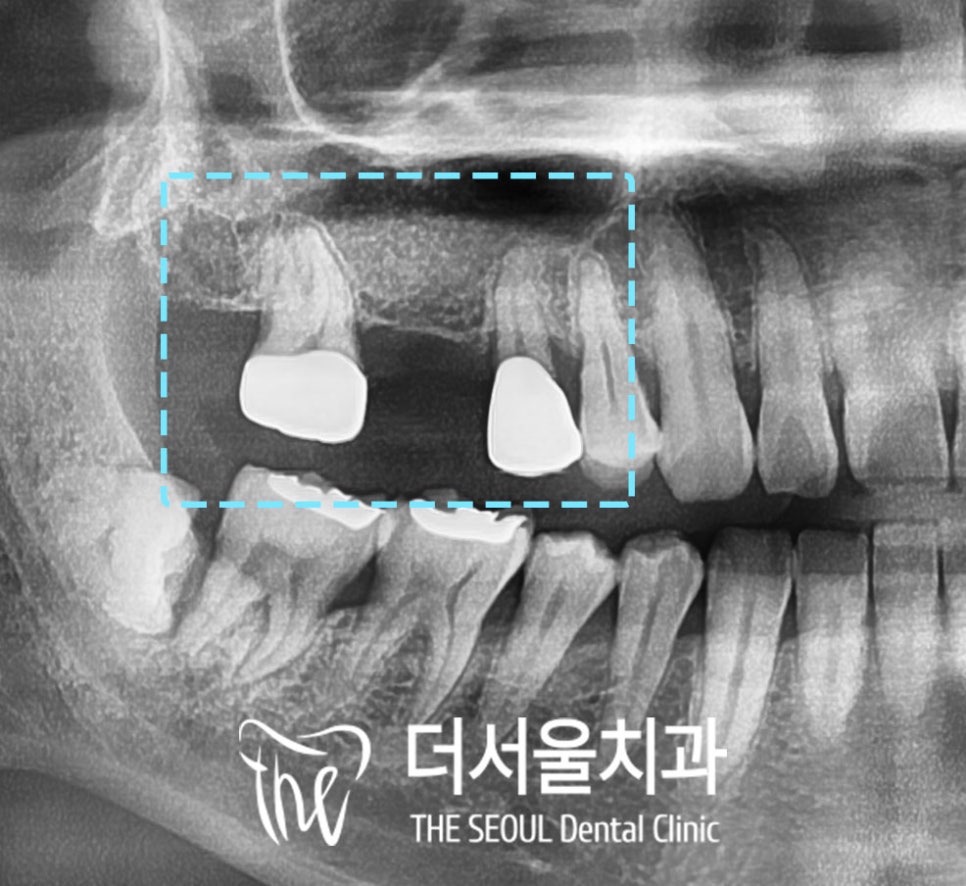

엑스레이 촬영을 해서 자세히 살펴보니

보철물과 잇몸 사이의 공간이 붕 떠있습니다.

그 안쪽으로 치석도 많이 쌓여있네요.

방사선 사진에서

양옆의 치아에 큰 문제가 없고

치근에도 염증이 있지는 않고..

우선 성남 임플란트가 가능한지 확인하기 위하여

CT 영상 촬영을 해보았습니다.

확실히 *상악동과 치조골간의 거리가 가까워

인공치근이 고정될 공간이 부족한건 사실입니다.